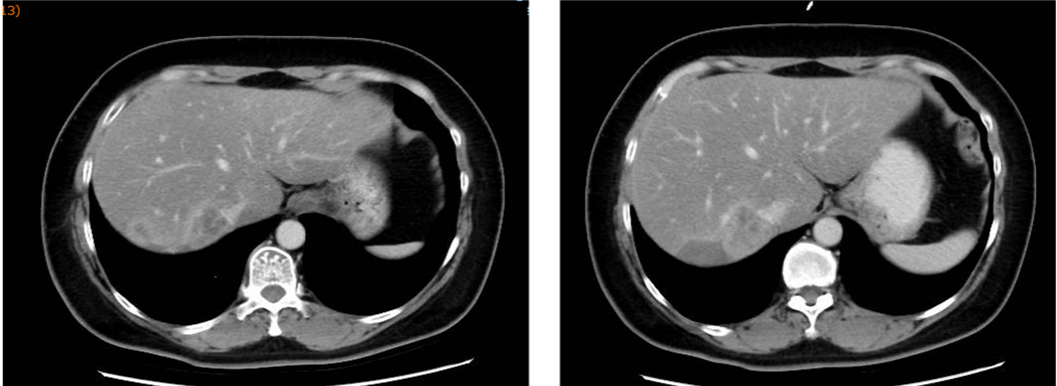

▌三线治疗:

入组MO28231临床试验,于2016-12-1开始行T-DM1治疗,具体:T-DM1 3.6mg/kg 237.6mg d1,Q21d。最佳评效PR。肝门区淋巴结自2019-6出现,逐渐增大,2019-11增大至29*22mm,考虑转移,判定为新发病灶PD出组,共治疗48周期,PD时间为2019-6,PFS为30月。不良反应:胆红素升高1级,血小板下降1级,疲劳1级,鼻出血1-2级,关节僵硬1级,手足麻木1级。

图4. 三线治疗